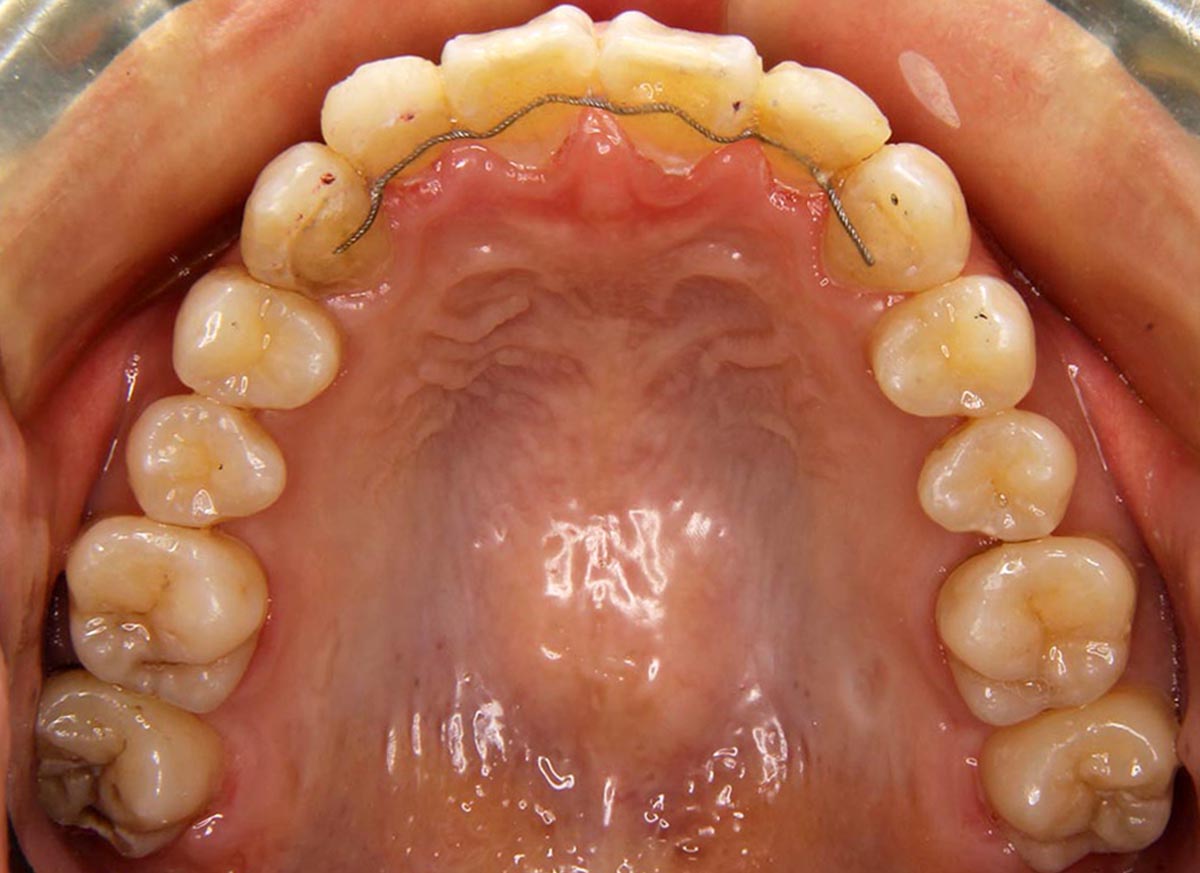

叢生(デコボコ)症例

●主訴

歯のデコボコが気になる

●診断

AngleⅠ級・前歯部叢生

●治療に用いた主な装置

上下顎にマルチブラケット装置(表側装置)

●抜歯部位

上下左右第一小臼歯4本

●治療期間

3年2ヶ月

●治療費用

約94万円(ともに税込、調整費、保定費まで含む総額制)

●付記

ひどいデコボコだったので拡大してからの抜歯治療になりました。リスクとして、

①歯根吸収…今回は全くありませんでした。

②カリエス(むし歯)…今回は治療途中でむし歯治療を行いました。

③あともどり…保定装置の装着をしっかりしていただいています。叢生(デコボコ)症例